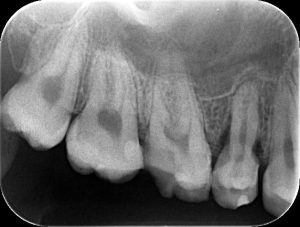

反対側の第2小臼歯にも進行したむし歯が認められ、エックス線写真を見ると、むし歯が歯冠だけでなく歯根の方にまで進行しており、感染歯質を除去するとほとんど歯が残らない状態であったため、抜歯せざるを得ないと判断しました。

抜歯をする前に、抜歯後どのような治療が望ましいか、検討するべきか、を必ず考えてから抜歯を行っていきますが、

この患者さんは若く、欠損治療のために歯を削りたくない、今後の歯列の変化に対応できるようにしたい、矯正治療もできるようにしておきたい、そして何といっても抜歯予定の歯の形態に近い過剰歯があるといった理由から、歯の移植を提案させていただき、当院の患者さんでもある親御さんも了承していただいたので、移植治療を進めていきました。